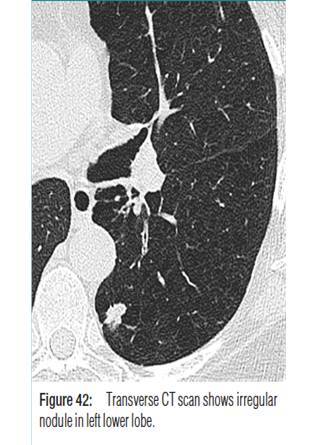

Define nodule, and mass

•Rounded opacities measuring up to 3 cm and greater than 3 cm, respectively.

What abnormality do you see here?